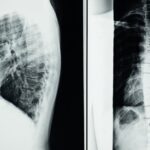

La décompression vertébrale consiste à appliquer une traction douce sur la colonne vertébrale. Elle vise à créer de l’espace entre les vertèbres, diminuant ainsi la compression sur les nerfs et les disques intervertébraux. Cette technique est souvent utilisée pour traiter des affections comme les hernies discales et les douleurs chroniques.

La décompression vertébrale est une méthode thérapeutique innovante qui cherche à soulager les douleurs chroniques liées à la colonne vertébrale. Elle est particulièrement efficace pour les personnes souffrant de hernies discales, de douleurs lombaires ou cervicales, ainsi que d’autres affections vertébrales. Ce traitement repose sur l’application d’une traction douce qui réduit la pression exercée sur les disques intervertébraux et les nerfs, permettant ainsi une guérison naturelle.

Un bombement discal est une déformation du disque intervertébral qui exerce une pression sur les nerfs environnants, causant des douleurs.